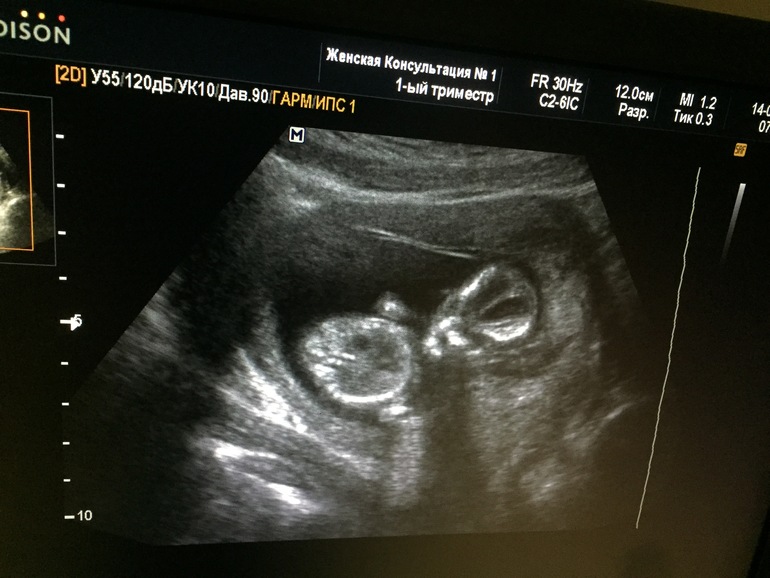

Всем привет)давно сюда не писала, время нет совсем)))были мы на первом скрининге)вроде по УЗИ сказали что все хорошо)и обрадовали мои тайные надежды))сказали что 100% сын)))ждать в гости 19 августа)))ростом мы уже 7 см с лишним, весим 71 грамм)носовую косточку нашли, сердечко бьется 157 ударов в минуту)))Пузико пока расти не думает, только маленький бугорок над лобком)тоска, ттт, как не было так и нет)грудь не болит почти)спал как папа, в итоге палец в рот и отвернулся))долго уговаривали перевернуться чтобы все померить)))вот как то так)))теперь ждём 1,5 месяца и на второе плановое УЗИ))а у вас как дела?)))у нас срок 13 и 3))